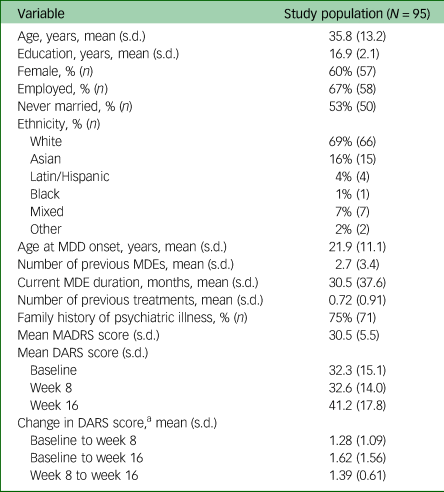

Demographic and clinical data are presented in Table 1.

Table 1 Baseline demographics of study population

MDD, major depressive disorder; MDE, major depressive episode; MADRS, Montgomery–Åsberg Depression Rating Scale; DARS, Dimensional Anhedonia Rating Scale.

a. Expressed as a fraction, final value divided by initial.